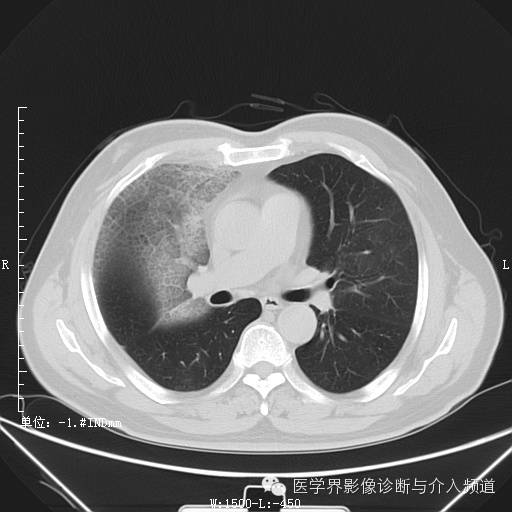

初诊

初诊:右肺上叶见大片实变影,呈磨玻璃状及网状,可见“充气支气管征”,纵隔窗可见实变影范围有所缩小,呈蜂窝状,局部支气管走行不自然,管壁不光滑。